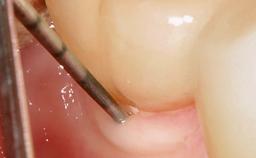

Peri-Implantitis Modified by the Presence of Submucosal Excess Cement: Reconstructive Therapy and a Ten-Year Follow-up

This case outlines the reconstructive therapy by Giovanni Salvi resulting in defect fill and inflammation-free peri-implant soft tissues at 10-year follow up. This case highlights the importance of regular monitoring of implants during supportive therapy.

A 30-year-old female patient was referred to the Department of Periodontology of the University of Bern, Switzerland, by a private dentist. Tooth 45 was congenitally missing and had been replaced with an implant three years prior to the first visit at the Department of Periodontology.